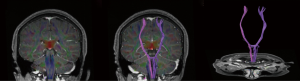

Routine laboratory tests were unremarkable, including liver and renal function, thyroid function, immunologic tests and serum ceruloplasmin level. The exception was a slightly elevated fasting serum glucose level (125 mg/dL). Transthoracic echocardiography was normal, and 24-hour Holter monitoring did not show arrhythmia. Subsequent brain magnetic resonance imaging at 3.0 T revealed acute ischemic stroke involving the left putamen (Figure 2) and periventricular area. However, magnetic resonance angiography did not show any stenosis in the left middle cerebral artery (Figure 3). Diffusion tensor imaging of the brainstem and cervical spine revealed normal cortico-spinal tract decussation in the lower medulla oblongata (Figure 4). The patient was diagnosed with acute onset post-stroke hemiballism that induced MM in her unaffected limb. She was given one week of clonazepam and haloperidol therapy, after which MMs and hemiballism nearly disappeared (Figure 5). The patient was discharged with standard ischemic stroke prevention measures including aspirin and atorvastatin. At follow-up 1 year later, no further episodes of involuntary movement had occurred.

Two main hypotheses have been put forward to explain the occurrence of MMs after stroke (10). One idea is that MMs depend on motor output from the voluntarily active primary motor cortex (M1) via functionally active ipsilateral spinal motoneurons. This abnormal projection may involve either branching of crossed corticospinal fibers or a separate ipsilateral corticospinal projection. A second idea is that MMs arise due to overactivation of the non-lesioned hemisphere during intended movement of the paretic hand. This overactivation may be due to dysfunction of the neural circuits that normally impose interhemispheric inhibition of motor planning processes. Since diffusion tensor imaging of our patient did not show any abnormal corticospinal decussation, and since MMs have been associated with dysfunction of the basal ganglia circuit (21), we speculate that acute putamen infarction may derepress interhemispheric inhibition and thereby contribute to MMs.